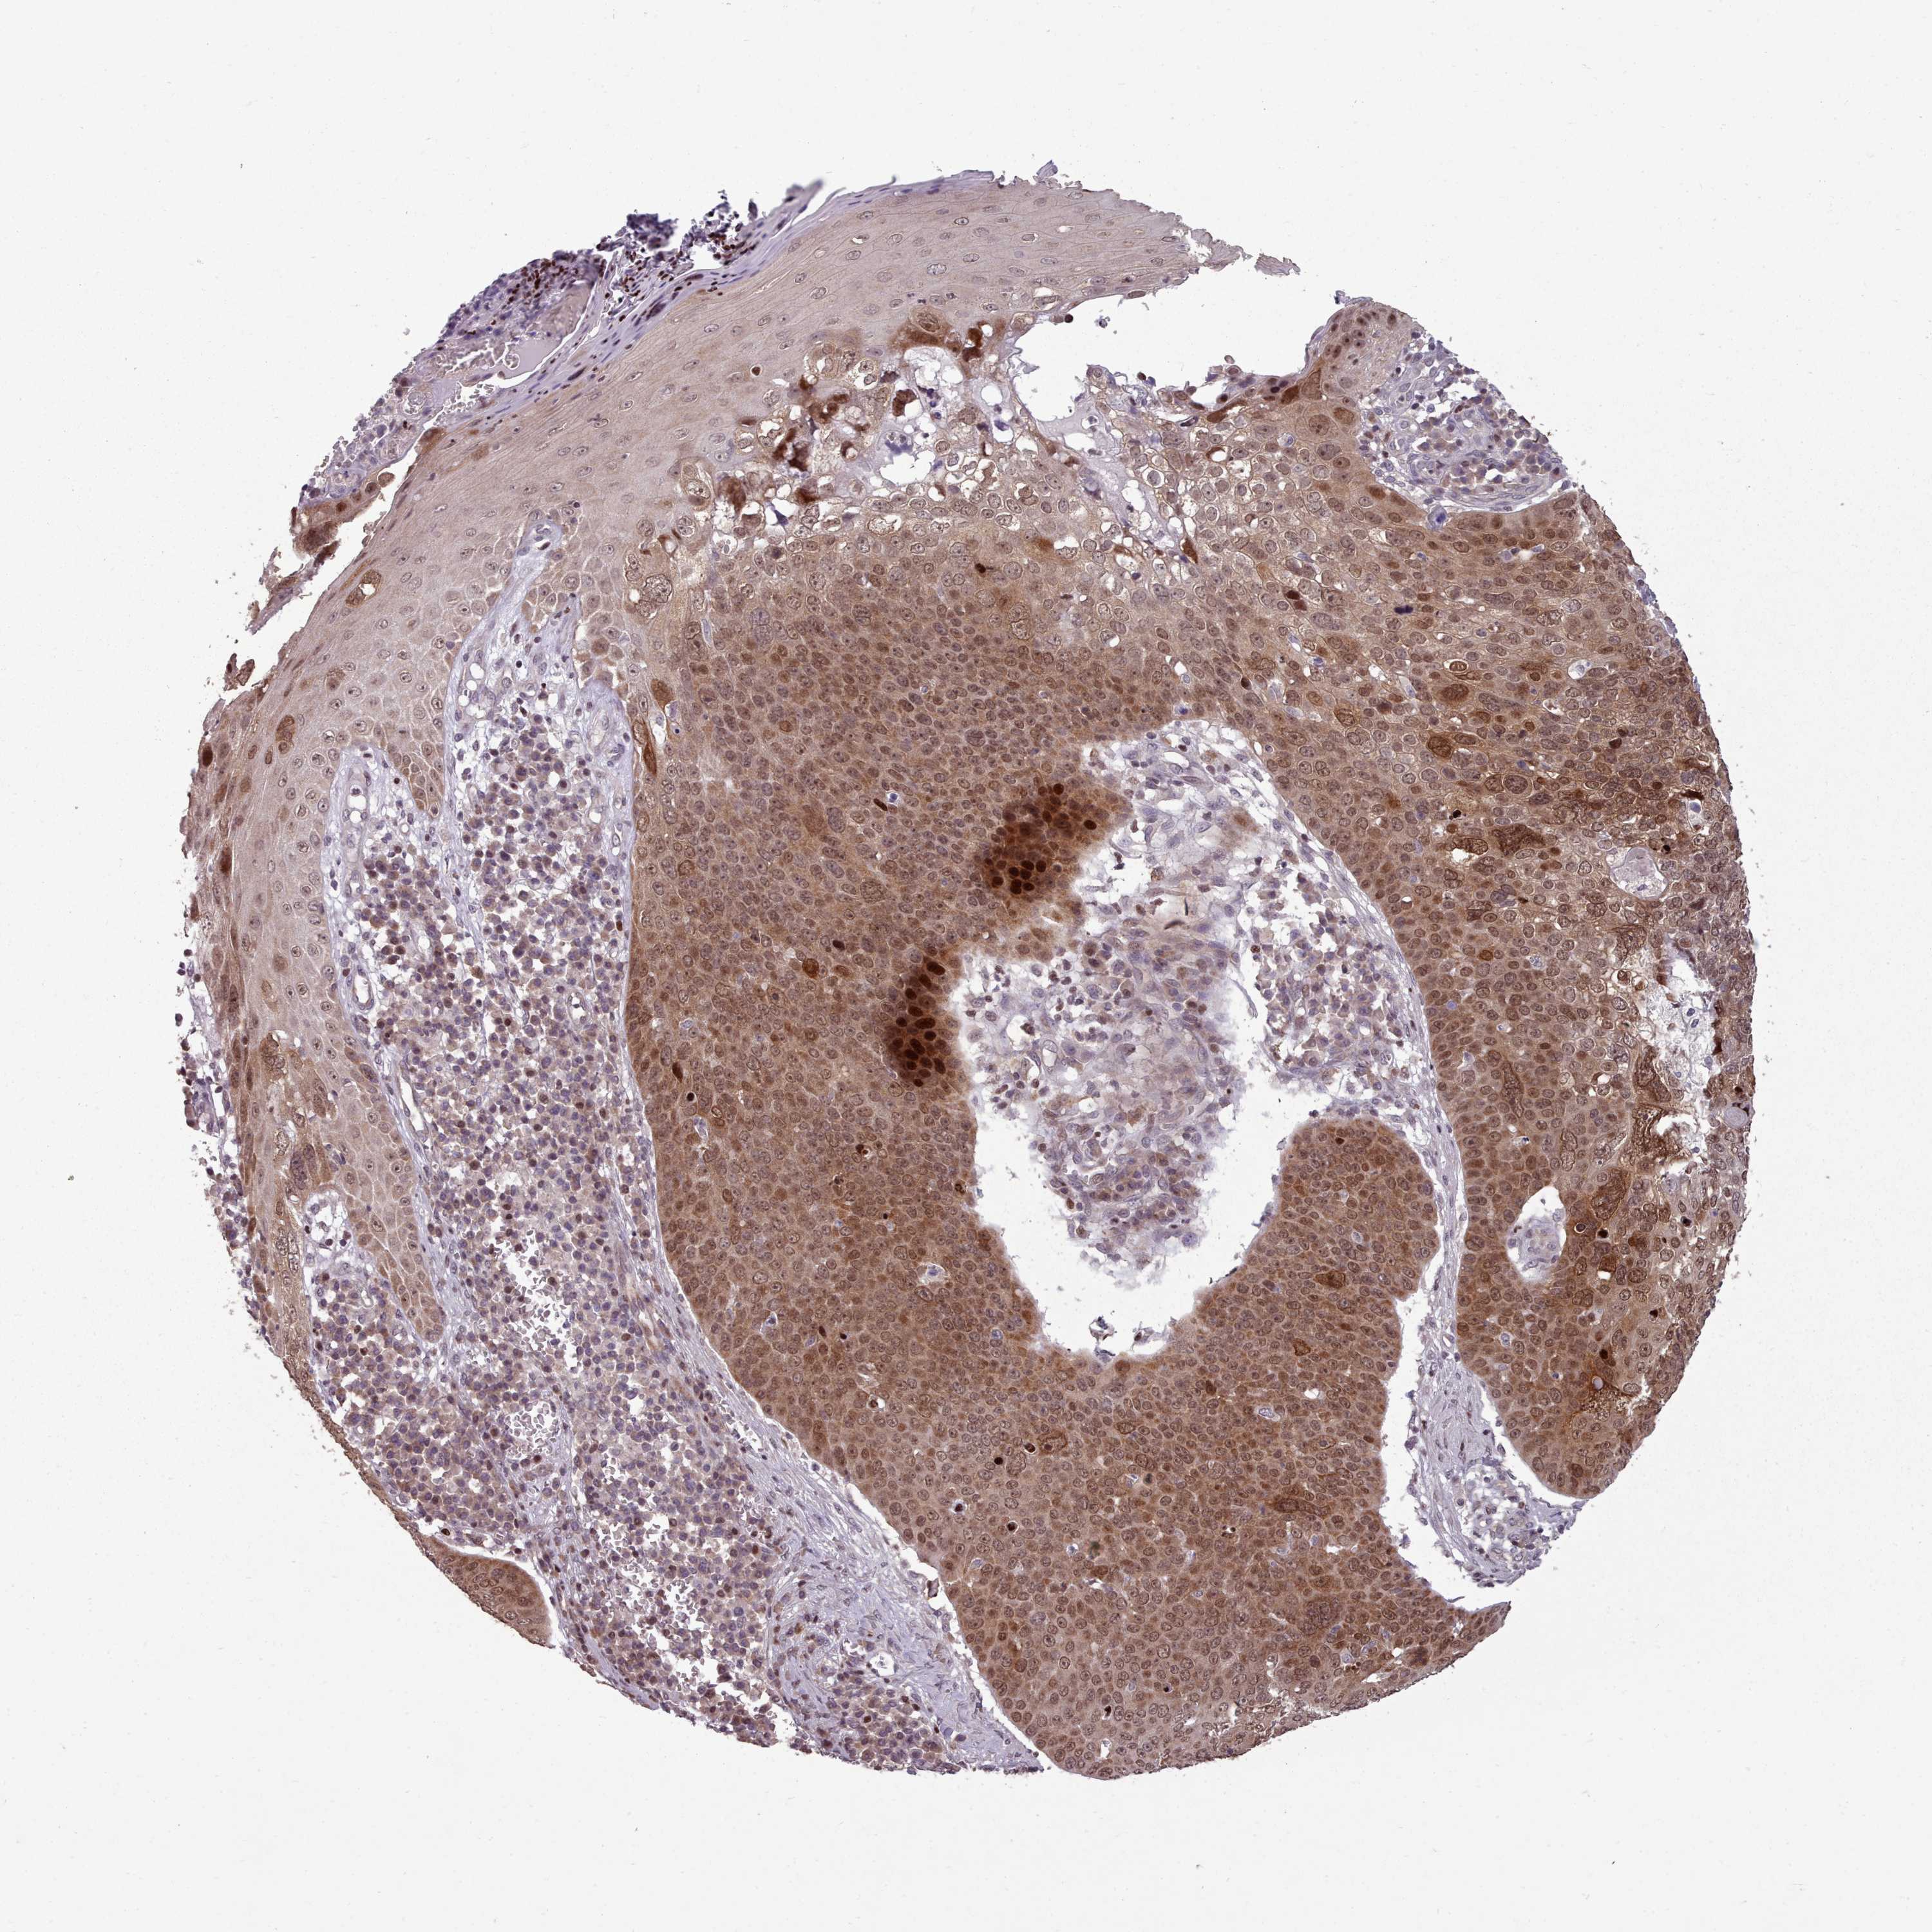

Basal cell and squamous cell cancer

SKIN CANCER - Protein expressioni

A mouse-over function shows sample information and annotation data. Click on an image to view it in a full screen mode. Samples can be filtered based on level of antibody staining by selecting one or several of the following categories: high, medium, low and not detected. The assay and annotation is described here.

Antibody stainingi

Antibody staining in the annotated cell types in the current human tissue is reported as not detected, low, medium, or high, based on conventional immunohistochemistry profiling in selected tissues. This score is based on the combination of the staining intensity and fraction of stained cells.

Each image is clickable and will lead to virtual microscopy that enables deeper exploration of all samples and also displays staining intensity scores, fraction scores and subcellular localization as well as patient and tissue information for each sample.

Antibody HPA051294

Staining

High

Medium

Low

Not detected

Intensity

Strong

Moderate

Weak

Negative

Quantity

>75%

75%-25%

<25%

None

Location

Nuclear

Cytoplasmic/membranous

Cytoplasmic/membranous,nuclear

Squamous cell carcinoma, NOS